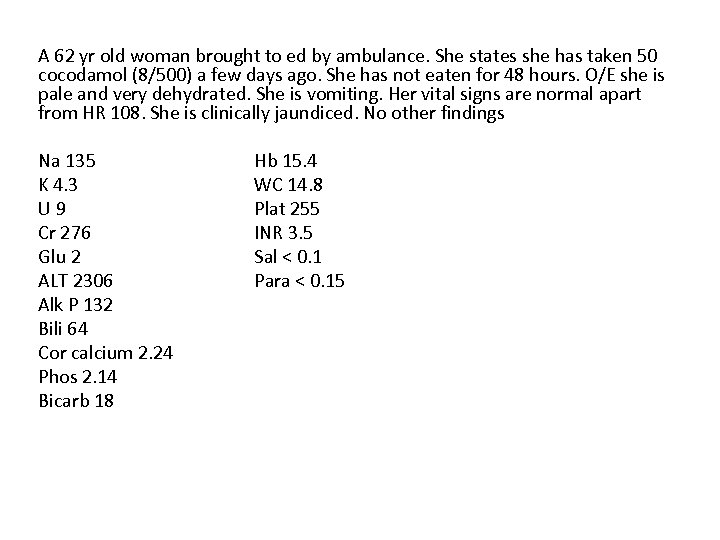

A 62 yr old woman brought to ed by ambulance. She states she has taken 50 cocodamol (8/500) a few days ago. She has not eaten for 48 hours. O/E she is pale and very dehydrated. She is vomiting. Her vital signs are normal apart from HR 108. She is clinically jaundiced. No other findings Na 135 K 4. 3 U 9 Cr 276 Glu 2 ALT 2306 Alk P 132 Bili 64 Cor calcium 2. 24 Phos 2. 14 Bicarb 18 Hb 15. 4 WC 14. 8 Plat 255 INR 3. 5 Sal < 0. 1 Para < 0. 15

Q 1. Why are bilirubin and ALT raised but not the alkaline phosphatase? (1 mark) Q 2. How is paracetamol metabolised and how does it cause damage in overdose? (2 marks)

Q 1. Why are bilirubin and ALT raised but not the alkaline phosphatase? (1 mark) • Bilirubin and ALT are markers of hepatic dysfunction and necrosis. (1/2 mark) • Alk Phos usually increases relatively little and is more associated with intra -hepatic obstruction or bile duct injury (1/2 mark) Q 2. How is paracetamol metabolised and how does it cause damage in overdose? (2 marks) • Toxic metabolite (NACQI) usually conjugated with glutathione and rendered harmless. • In overdose, or reduced glutathione stores, the toxic metabolite binds to cells and leads to cell death , centrilobular necrosis (1 mark for each answer)